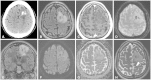

The imaging and clinical management of patients with brain tumor continue to evolve over time and now heavily rely on physiologic imaging in addition to high-resolution structural imaging. Imaging remains a powerful noninvasive tool to positively impact the management of patients with brain tumor. This article provides an overview of the current state-of-the art clinical brain tumor imaging. In this review, we discuss general magnetic resonance (MR) imaging methods and their application to the diagnosis of, treatment planning and navigation, and disease monitoring in patients with brain tumor. We review the strengths, limitations, and pitfalls of structural imaging, diffusion-weighted imaging techniques, MR spectroscopy, perfusion imaging, positron emission tomography/MR, and functional imaging. Overall this review provides a basis for understudying the role of modern imaging in the care of brain tumor patients.